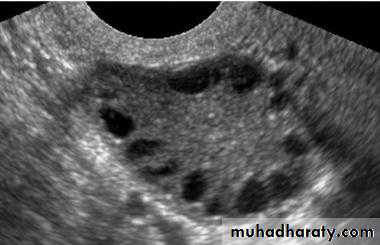

US of PCOSPCOS

In PCOS monophasic follicles